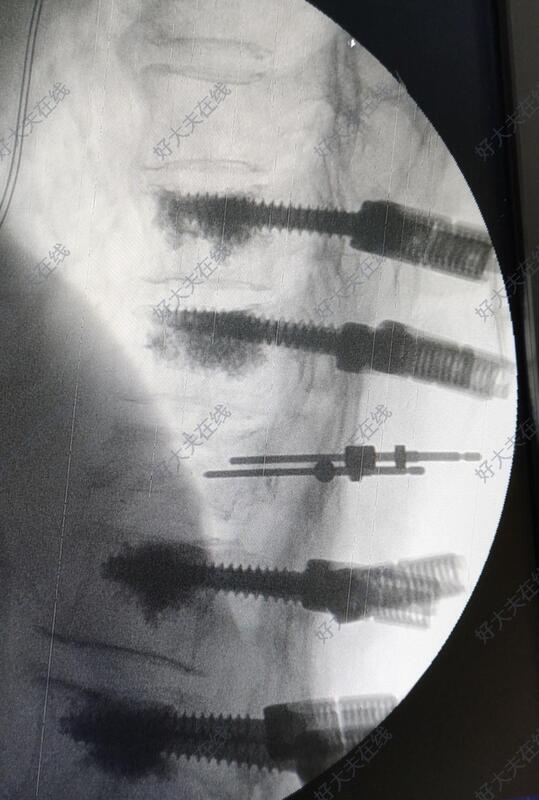

术中于胸10,胸11,腰1,腰2椎体置入骨水泥椎弓根螺钉。透视见骨折复位后,于胸12双侧椎弓根对胸12椎体植骨。

术后3月左右患者来门诊随访。腰背部疼痛完全消失,双下肢活动良好,自行步入病室,步态稳定,患者自觉恢复良好。复查X线提示内固定位置良好,胸腰椎后凸畸形恢复良好。